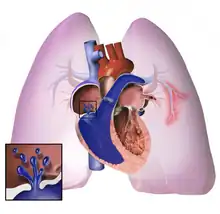

The pathogenesis of pulmonary arterial hypertension (WHO Group I) involves the narrowing of blood vessels connected to and within the lungs. This makes it harder for the heart to pump blood through the lungs, as it is much harder to make water flow through a narrow pipe as opposed to a wide one. Over time, the affected blood vessels become stiffer and thicker, in a process known as fibrosis. The mechanisms involved in this narrowing process include vasoconstriction, thrombosis, and vascular remodeling (excessive cellular proliferation, fibrosis, and reduced apoptosis/programmed cell death in the vessel walls, caused by inflammation, disordered metabolism and dysregulation of certain growth factors).[26][27] This further increases the blood pressure within the lungs and impairs their blood flow. In common with other types of pulmonary hypertension, these changes result in an increased workload for the right side of the heart.[15][28] The right ventricle is normally part of a low pressure system, with systolic ventricular pressures that are lower than those that the left ventricle normally encounters. As such, the right ventricle cannot cope as well with higher pressures, and although right ventricular adaptations (hypertrophy and increased contractility of the heart muscle) initially help to preserve stroke volume, ultimately these compensatory mechanisms are insufficient; the right ventricular muscle cannot get enough oxygen to meet its needs and right heart failure follows.[15][27][28] As the blood flowing through the lungs decreases, the left side of the heart receives less blood. This blood may also carry less oxygen than normal. Therefore, it becomes harder and harder for the left side of the heart to supply sufficient oxygen to the rest of the body, especially during physical activity.[29][30][10] During the end-systolic volume phase of the cardiac cycle, the Gaussian curvature and the mean curvature of right ventricular endocardial wall of PH patients was found to be significantly different as compared to controls.[31]